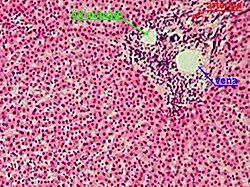

Qaraciyər toxuması

Paycıqlar

Çoxguşəli ulduz şəkilli Kupfer hüceyrələri

Portal triada – Qlisson üçlüyü

Qaraciyər mürəkkəb borulu vəzilərdən olub, bir çox paycıqlardan – lat. lobuli hepatis ibarətdir. Paycıqları təşkil edən atmalar qaraciyər epitel hüceyrələrindən əmələ gəlmişdir. Qaraciyər paycıqları şəkilcə çoxbucaqlı olub, bir-biri ilə birləşdirici toxuma vasitəsilə birləşmişdir. Paycıqların daxilində retikulyar liflərdən təşkil olunmuş tor vardır; bu liflər, ehtimal ki, qaraciyər kapillyarları endotelinin törəmələridir. Həmin endotel faqositoz vəzifəsinə malik ulduzabənzər (Kupfer adlanan) hüceyrələrdən ibarətdir.